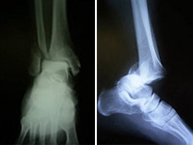

La articulación del tobillo une la pierna con el pie y su funcionamiento permitela normal deambulación que realizamos. Están implicados los tercios inferiores de la tibia y el peroné que articulan con el astrágalo del pie. Es una región anatómica muy susceptible de recibir lesiones fundamentalmente de dos tipos; alta energía en accidentes laborales o de tráfico produciendo las temibles fracturas de pilón tibial o de baja energía en el ámbito deportivo por mecanismos de torsión produciendo las fracturas maleolares. Las fracturas de pilón tibial se acompañan de gran afectación de los tejidos circundantes al hueso por lo que requieren un tratamiento muy meticuloso de estos tejidos antes de resolver la lesión ósea. En las fracturas maleolares, características de deportes de salto y giro como fútbol, basket, monopatín, volley, artes marciales, etc., la lesión se produce a nivel del mecanismo de pinza conocido como mortaja tibioastragalina que impide en condiciones normales que el pie se separe de la pierna.Las lesiones del tobillo, como en general de todas las articulaciones del esqueleto, requiere una reconstrucción anatómica para evitar la rigidez articular por lo que se realizará una cirugía rápida y mínimamente invasiva para reincorporar al paciente lo antes posible a su actividad previa.